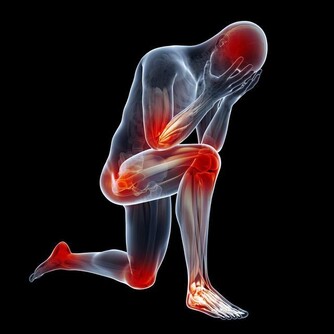

五十肩不一定發作於五十歲

經常「肩膀痛」或「手不舉」嗎?五十肩找上門來怎麼辦?

事實上,五十肩的英文名詞是:「冰凍肩」(frozen shoulders),

它的正確名稱是:「粘連性肩關節囊炎(adhesive capsulitis)」簡單說來,

就是關節囊重複累積各種酸痛、發炎後,最後被僵硬的軟組織夾擊,導致關節無法活動。

雖然這種症狀好發於40-60歲之間的族群,但年齡只是參考,

越來越多人年輕人發現手臂「忽然不舉」,才知道竟然是五十肩發作。